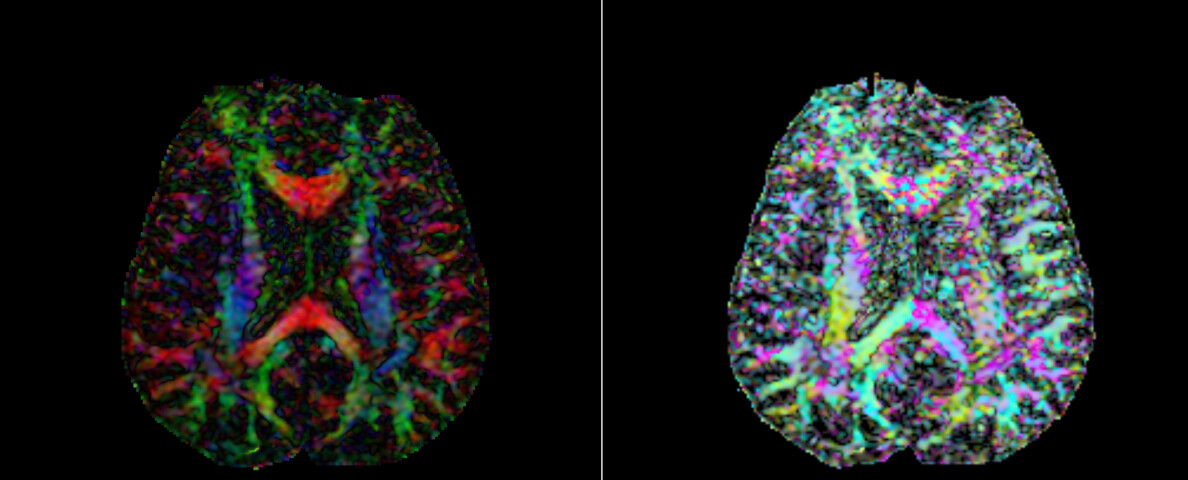

问题描述:自己用程序对对原始数据进行处理在张量拟合后生成dti.nhdr文件,与用3D Slicer对原始数据进行处理后生成的dti.nhdr文件在Slicer软件中打开效果不一样,如下图

你的截图(左:Slicer自带模型生成;右:你自己的程序生成)说明——张量场虽然成功导入,但 方向、缩放或空间信息存在不一致。

颜色分布相似但方向错乱(左绿右粉、前红后蓝)

你的情况(颜色方向错乱)最可能的原因是 measurement frame 或 space directions 不匹配。